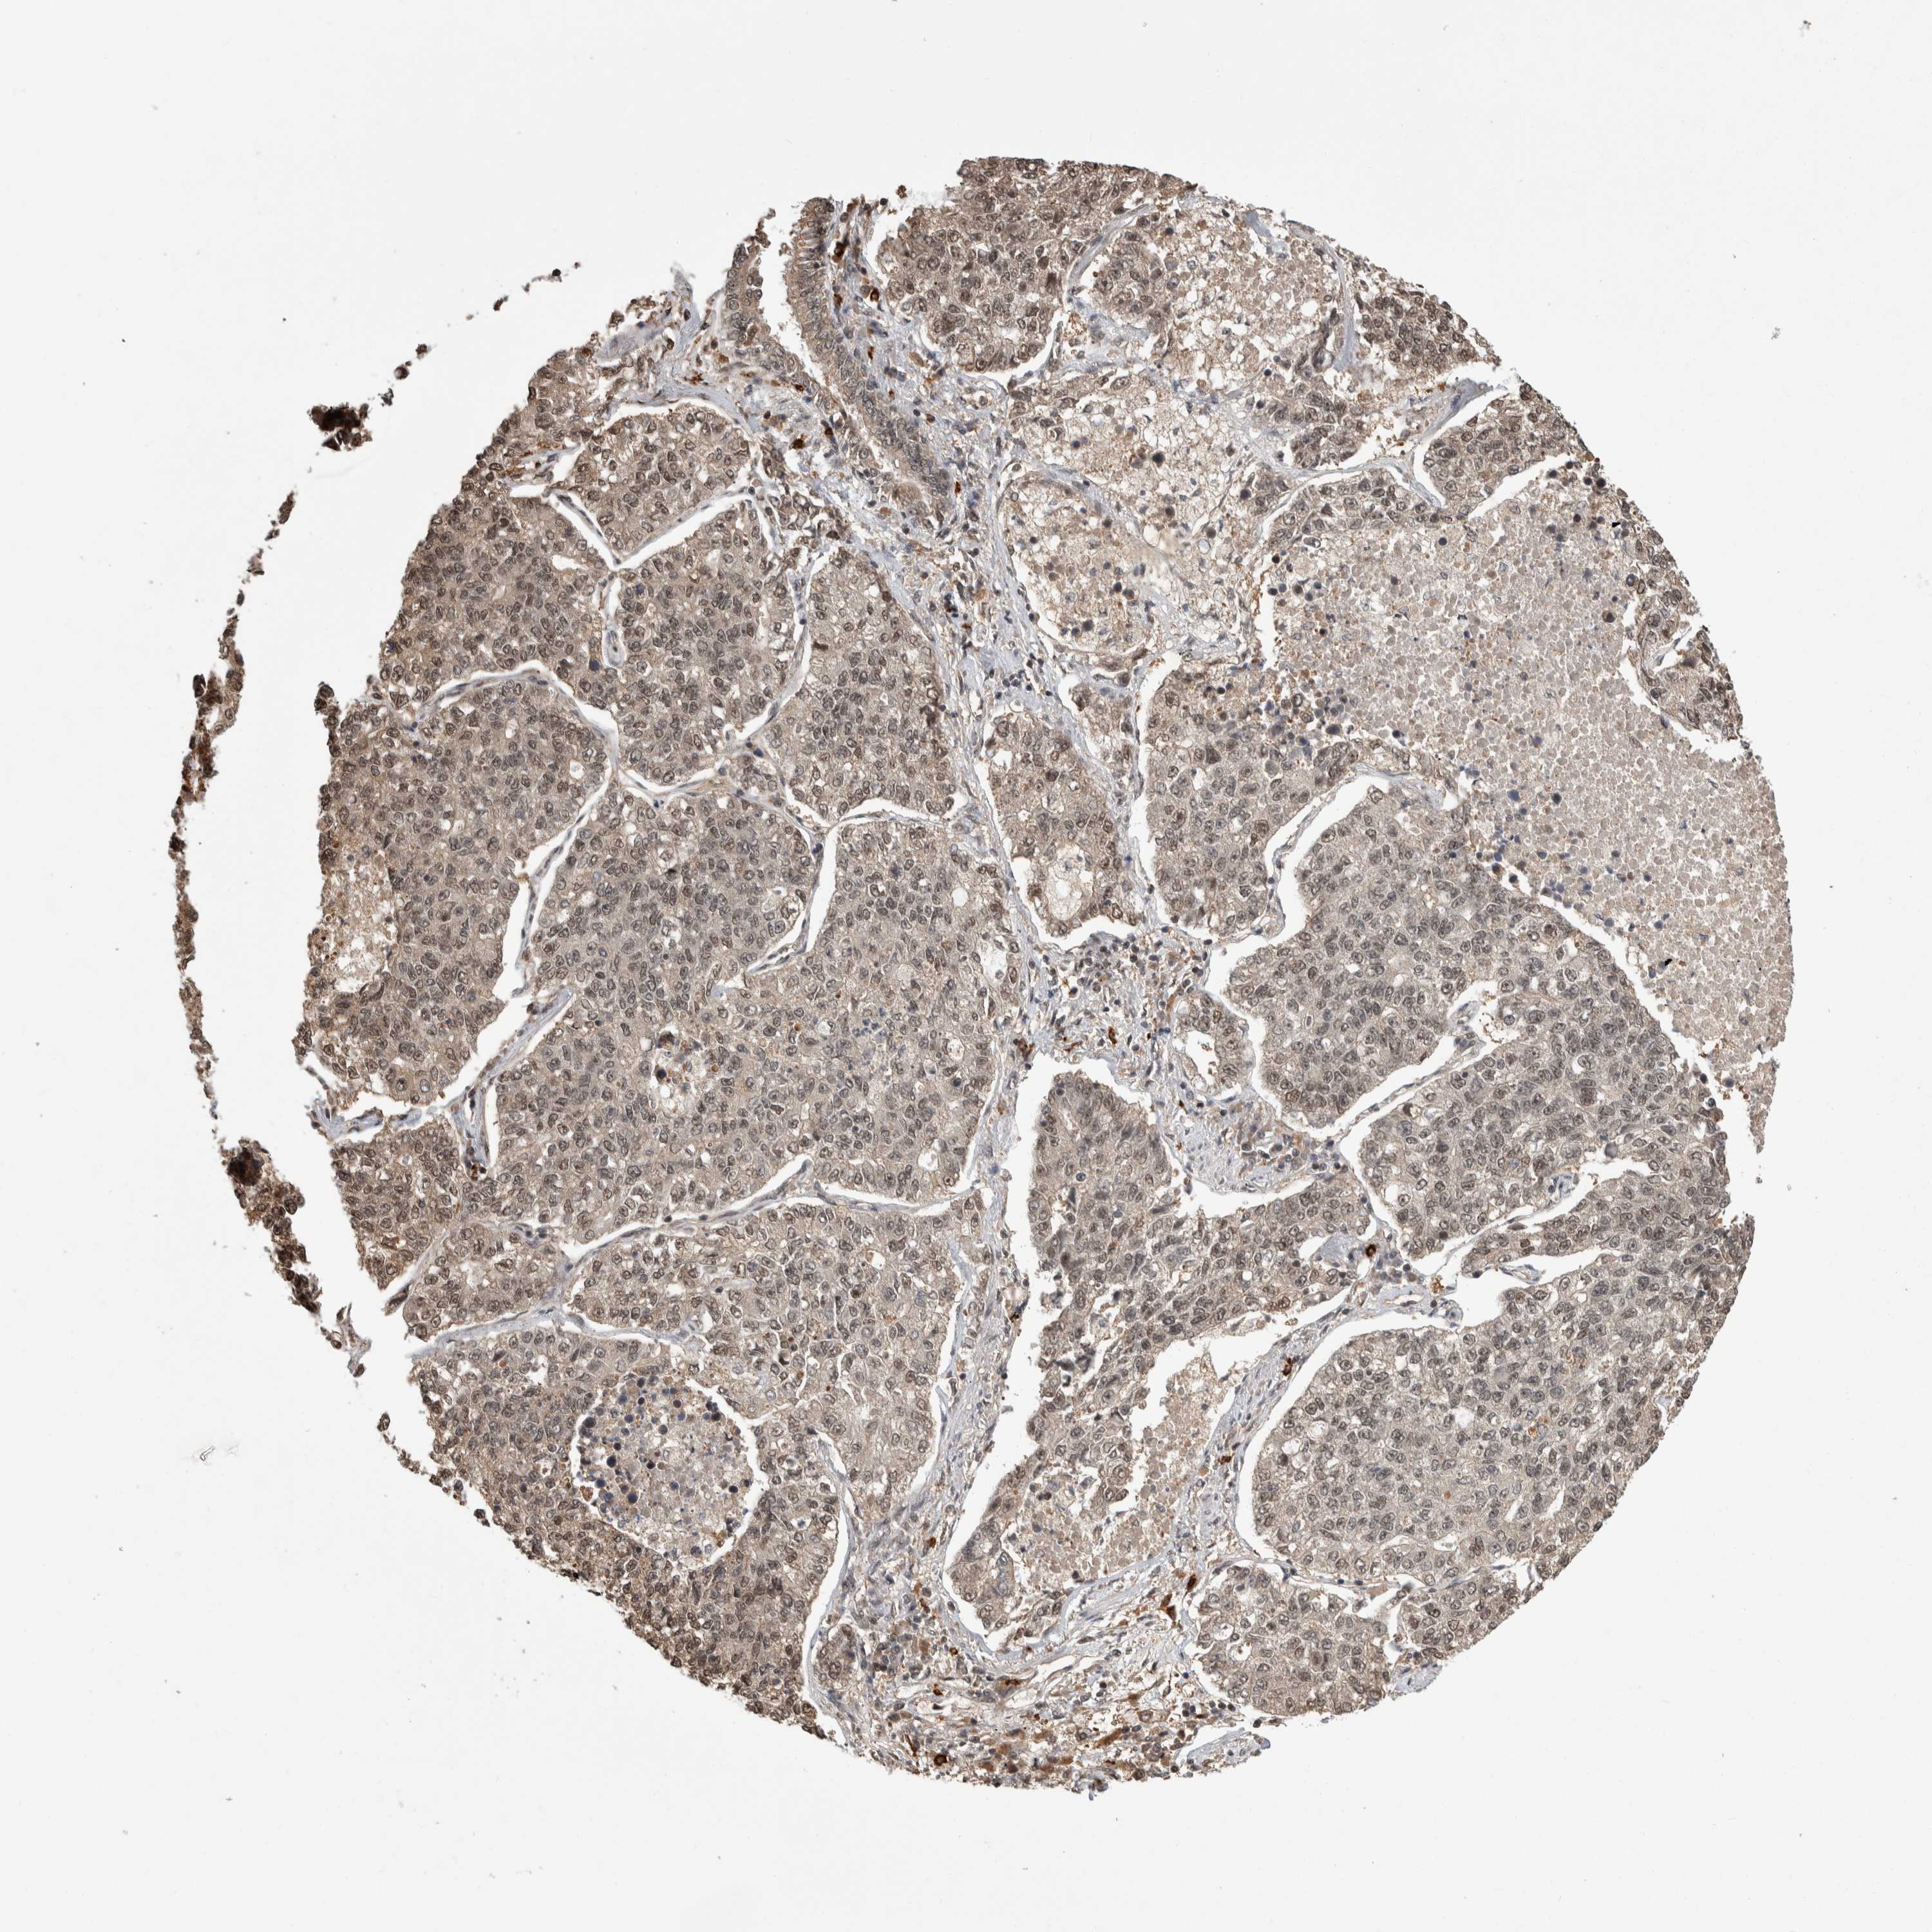

CANCER LUNG CANCER Show tissue menu

LUAD TCGA LUAD VALIDATION LUSC TCGA LUSC VALIDATION PROTEIN LUAD CPTAC PROTEIN LUSC CPTAC PROTEIN EXPRESSION

Lung cancer

Human cancer

Lung adenocarcinoma

Lung squamous cell carcinoma